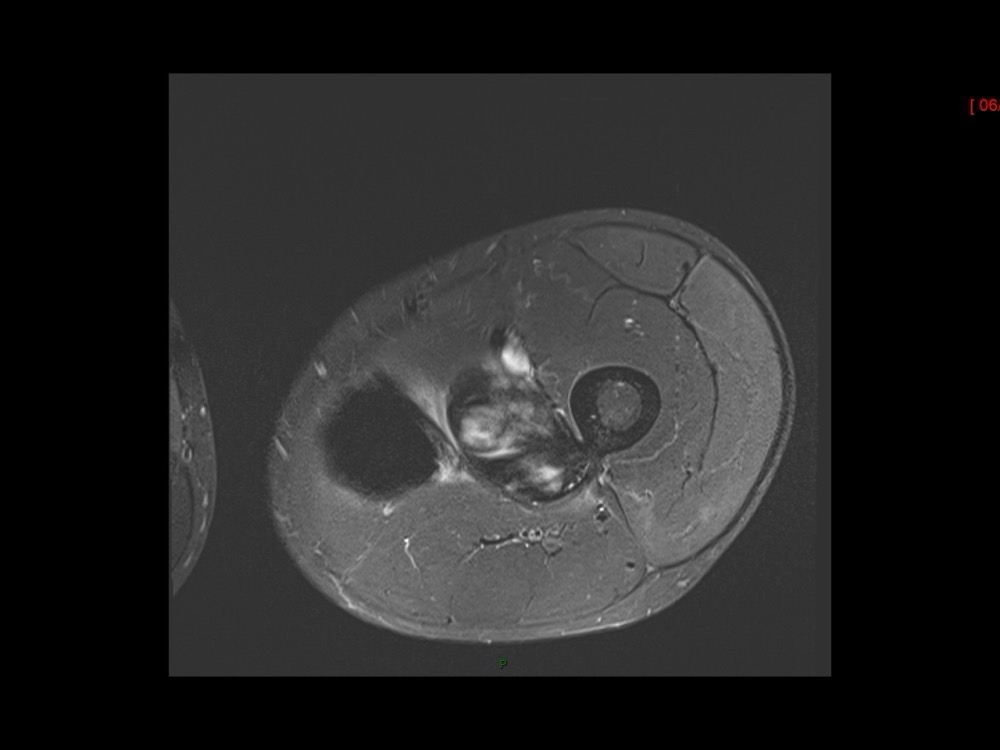

Moalla / Mihoubi-Bouvier / Drapé 18/05/2022